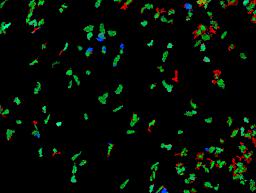

Pancreatic ductal adenocarcinoma is a lethal disease with limited treatment options and poor survival. We studied 83 spatial samples from 31 patients (11 treatment-naïve and 20 treated) using single-cell/nucleus RNA sequencing, bulk-proteogenomics, spatial transcriptomics and cellular imaging. Subpopulations of tumor cells exhibited signatures of proliferation, KRAS signaling, cell stress and epithelial-to-mesenchymal transition. Mapping mutations and copy number events distinguished tumor populations from normal and transitional cells, including acinar-to-ductal metaplasia and pancreatic intraepithelial neoplasia. Pathology-assisted deconvolution of spatial transcriptomic data identified tumor and transitional subpopulations with distinct histological features. We showed coordinated expression of TIGIT in exhausted and regulatory T cells and Nectin in tumor cells. Chemo-resistant samples contain a threefold enrichment of inflammatory cancer-associated fibroblasts that upregulate metallothioneins. Our study reveals a deeper understanding of the intricate substructure of pancreatic ductal adenocarcinoma tumors that could help improve therapy for patients with this disease.